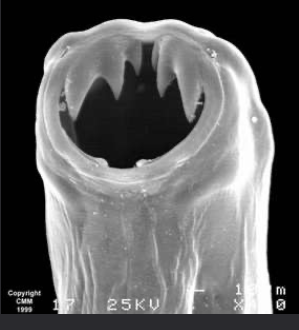

hookworms

Human and animal parasite

The hookworm will feed in the intestine’s of the host. It will feed on blood and are quite wasteful so if the host has lots of hook worm, it can lead to anaemia. Serious infections of hook worm in children can affect the growth physically and mentally. Hook worm can also cause death in puppies and young animals